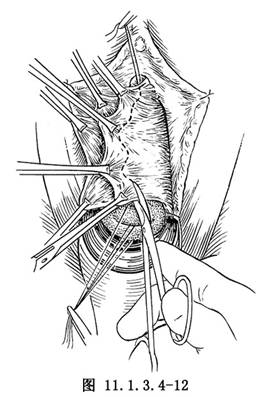

(6)剪去多餘部分之陰道黏膜(圖11.1.3.4-12),以可吸收線或2-0號鉻制腸線,相對間斷縫合陰道黏膜,穿過一點其下的筋膜,避免形成死腔(圖11.1.3.4-13)。